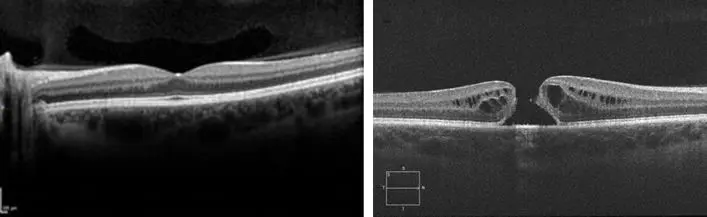

Izquierda: Mácula Normal | Derecha: Agujero Macular

AGUJERO MACULAR

Se define como agujero macular a la pérdida de espesor completo del centro de la retina, zona que llamamos mácula, y se presenta de forma idiopática (influenciada por la edad, desprendimiento del vítreo que se contrae y tracciona el centro de la retina), y otras formas como traumática (un golpe fuerte), por miopia,entre otras.

Similar a la degeneración macular asociada a la edad, los síntomas que producen son en el centro de la visión (deformación al visualizar líneas, dificultad para enfocar el centro de las cosas).

El tratamiento actual es quirúrgico, mediante un procedimiento llamado vitrectomía. En esta cirugía se realiza un peeling de la capa más superficial de la retina y se coloca una burbuja de gas, la cual empujará la zona reparada y mejorará la probabilidad de que el agujero cierre.

Una vez que se desarrolla esta enfermedad, la posibilidad de curación espontánea sin tratamiento es muy poco frecuente, por este motivo, una vez diagnosticado, se le indicará cirugía para corregir la pérdida de tejido.

IMPORTANTE: AL IGUAL QUE EN MUCHAS ENFERMEDADES QUE OCURREN EN UN SOLO OJO, MUCHAS VECES LOS SÍNTOMAS PASAN DESAPERCIBIDOS A NO SER QUE UNO SE TAPE UN OJO Y VERIFIQUE LA DIFERENCIA ENTRE AMBOS OJOS, PORQUE CON LOS DOS OJOS ABIERTOS MUCHAS VECES NO NOTAMOS LA DIFERENCIA